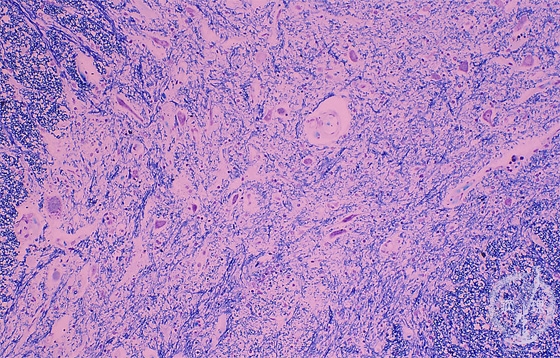

Microscopic findings (H.E. low magnification): The number of anterior-horn neurons was reduced with marked gliosis. Remaining neurons were atrophic.